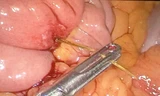

Quá trình mổ, ekip xẻ ổ áp xe lấy ra khoảng 50ml mủ xanh đục, bên trong đó có 1 dị vật là chiếc tăm tre nhọn dài khoảng 6,5cm; tiếp tục xẻ tĩnh mạch chủ dưới lấy ra đoạn huyết khối dài khoảng 4cm.

![]() |

| Chiếc tăm tre được lấy ra khỏi cơ thể bệnh nhân. |